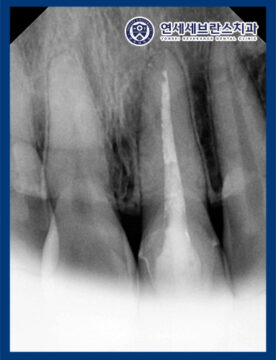

25.12.22

<보이지 않던 포스트 발견>

이렇게 당일 응급으로 재신경치료를 시작했는데,

명확히 보이지 않던 포스트를 발견하여

다음번 크라운 제거 및 포스트 제거를

시도해 보기로 하였습니다.